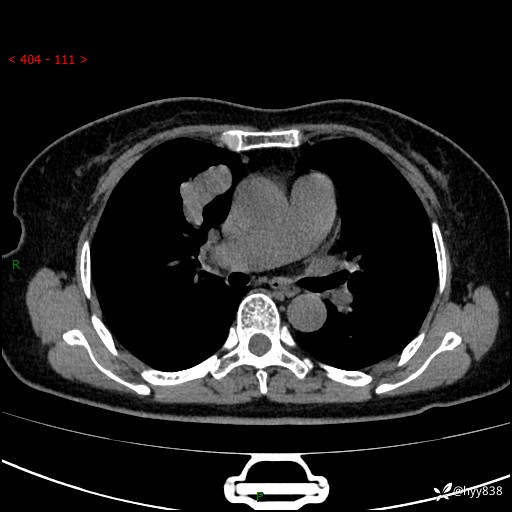

【患者信息】:70岁/女

【主诉】:发现右上肺肿物10天

【现病史及既往史】:者10天前因“背部酸痛”于当地治疗,无发热,无呕吐,无头痛头晕等不适,胸部CT示右上肺肿物。遂来我科就诊,门诊看过病人后以“”收入我科, 自患病以来,精神、饮食、睡眠尚可,大小便正常,体力体重无明显减轻。

【检查】:胸部CT平扫(患者过敏体质,不能增强)